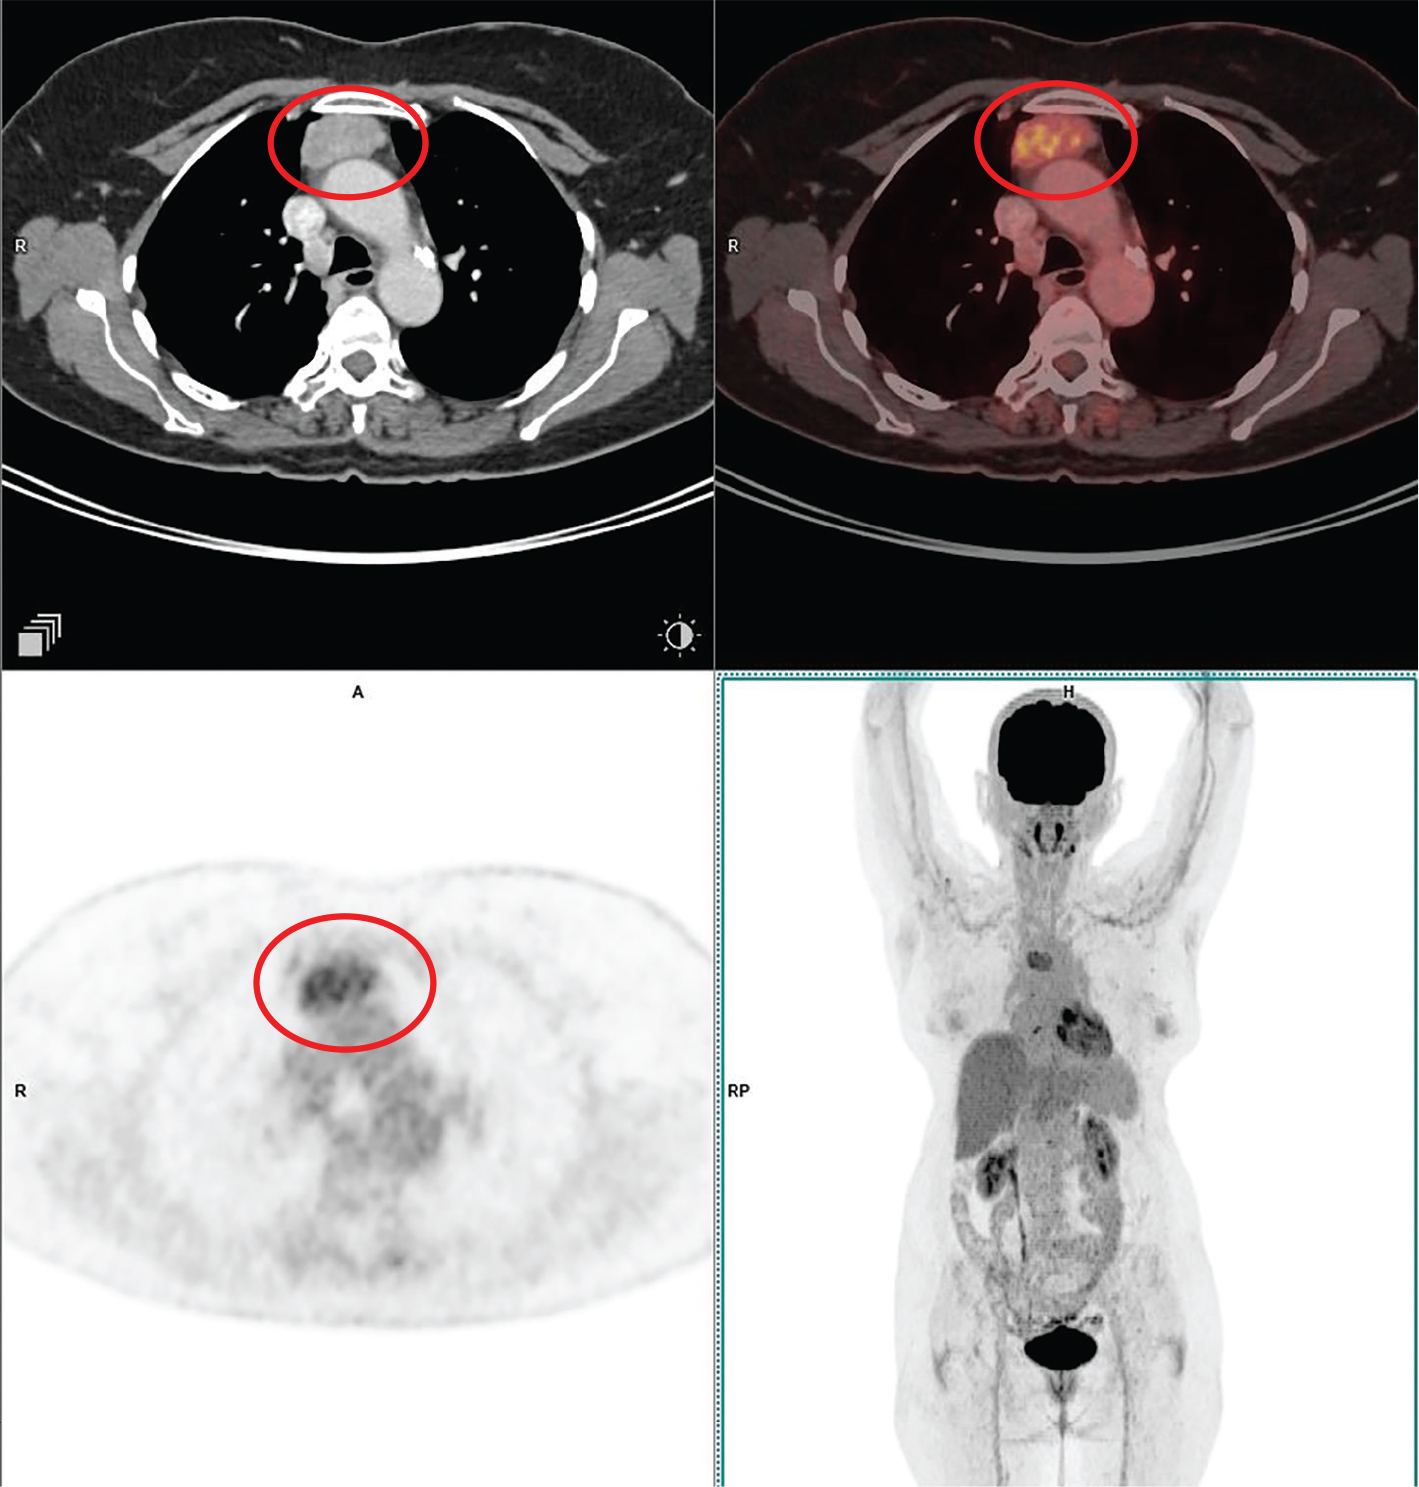

Aggressive thymic epithelial tumors frequently invade or extrinsically compress the superior vena cava (SVC), causing SVC syndrome. Thymic carcinomas typically exhibit more irregular contours, heterogeneity related to hemorrhage, necrosis, and cystic change, as well as higher levels of local vascular and mediastinal invasion and lymphadenopathy (3032). An example of thymic carcinoma is shown in Figure 2.

Fig 2

Figure 2. Thymic carcinoma. Anterior mediastinal mass that was pathologically confirmed as thymic carcinoma. FDG PET/CT images include axial CT (top left panel), fused axial PET/CT (top right panel), axial PET (bottom left panel), and maximum intensity projection (MIP) PET image (bottom right panel). In the red circle, there is a soft tissue density mass with irregular nodular contour showing heterogenous enhancement in CT with heterogenous FDG uptake on PET. There is loss of intervening fat plane with the body of sternum anteriorly and the pulmonary trunk posteriorly concerning for infiltration. There was additional mild to moderately FDG-avid regional lymph nodes and pleural deposits (not on the included PET/CT images and could be appreciated on the MIP image) that were suggestive of metastatic disease.